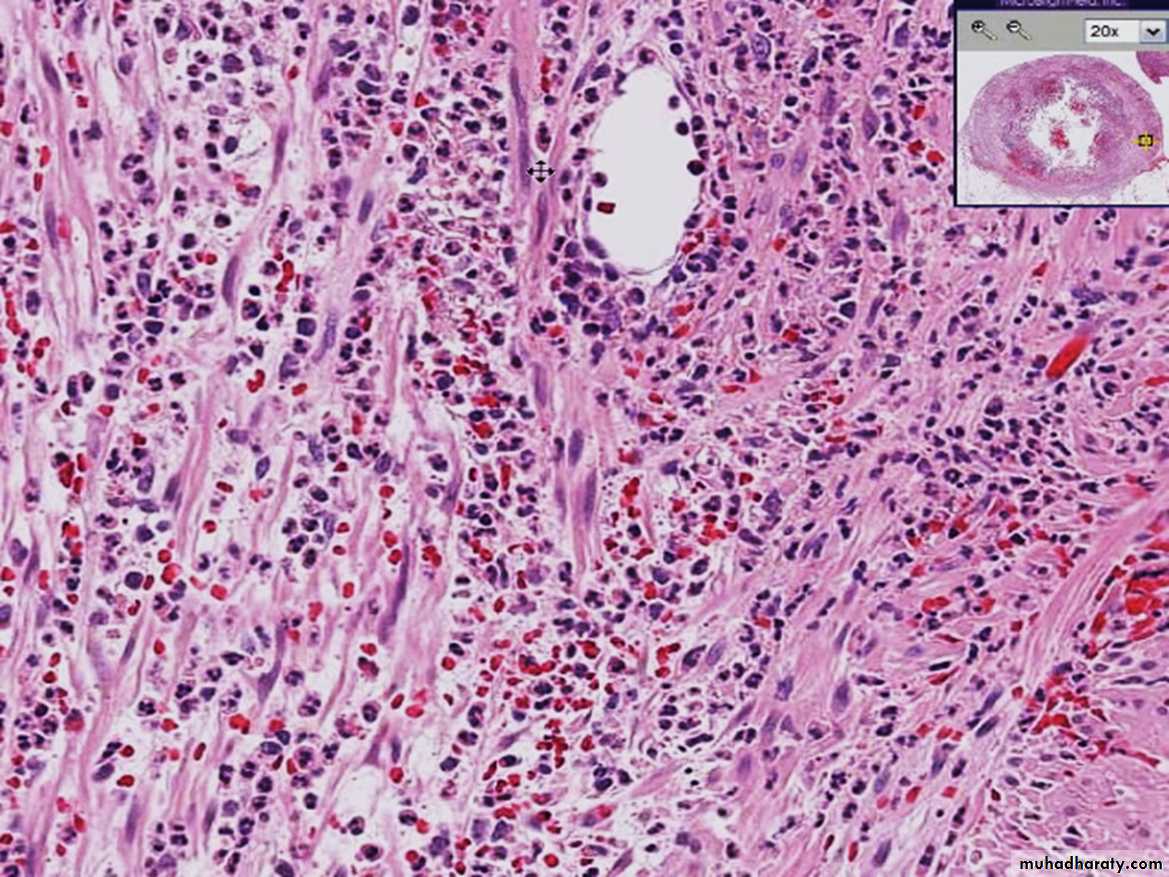

Acute & CHRONIC

Inflammation

Acute appendix